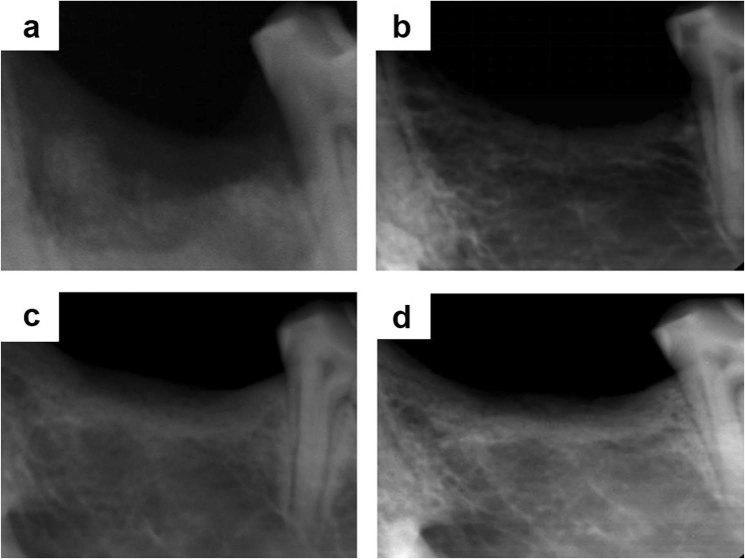

Over the past years, the study about bone tissue engineering in the field of regenerative medicine has been a main research topic. Using three-dimensional (3D) porous degradable scaffold complexed with mesenchymal stem cells (MSCs) and growth factor gene to improve bone tissue repair and regeneration has raised much interest. This study mainly evaluated the osteogenesis of alveolar bone defects of animal in the following experimental groups: sham-operated (SO), 3D printed bioglass (3D-BG), 3D-BG with BMP-2 gene loaded CS (3D-BG + BMP/CS) and 3D-BG with rhesus marrow bone MSCs and BMP/CS (3D-BG + BMP/CS + rBMSCs). Simulated human bone defect with critical size of 10 × 10 × 5 mm were established in quadrumana - rhesus monkeys, and in vivo osteogenesis was characterized by X-ray, micro-Computed Tomography (mCT) and history. Our results revealed that 3D-BG + rBMSCs + BMP/CS scaffold could improve bone healing best by showing its promote osteogenic properties in vivo. Considering the great bone repair capacity of 3D-BG + BMP/CS + rBMSCs in humanoid primate rhesus monkeys, it could be a promising therapeutic strategy for surgery trauma or accidents, especially for alveolar bones defects.

在过去的几年中,再生医学领域中关于骨组织工程的研究一直是主要研究课题。使用三维(3D)多孔可降解支架与间充质干细胞(MSCs)和生长因子基因复合,以改善骨组织修复和再生,引起了广泛关注。本研究主要评估了以下实验组动物牙槽骨缺损的成骨作用:假手术(SO)、3D 打印生物玻璃(3D-BG)、负载 BMP-2 基因的 3D-BG 与壳聚糖(3D-BG+BMP/CS)和负载恒河猴骨髓间充质干细胞和 BMP/CS 的 3D-BG(3D-BG+BMP/CS+rBMSCs)。在四足动物 - 恒河猴中建立了模拟人类具有临界尺寸为 10×10×5mm 的骨缺损,并通过 X 射线、微计算机断层扫描(mCT)和组织学特征来描述体内成骨作用。我们的结果表明,3D-BG+rBMSCs+BMP/CS 支架通过显示其在体内的促骨生成特性,可以最好地改善骨愈合。考虑到 3D-BG+BMP/CS+rBMSCs 在类人灵长类恒河猴中具有很强的骨修复能力,它可能是一种有前途的治疗手术创伤或事故,特别是牙槽骨缺损的治疗策略。